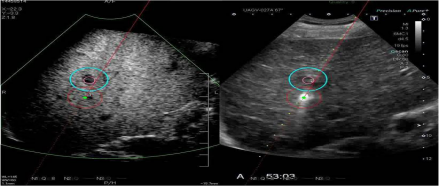

2. 全面的造影功能(Contrast Enhancement Ultrasound):系统可以四幅图(二维, 造影, 微血管累积模式MFI/到达时间参数成像P-MFI, 混合模式)同时显示,方便进行介入治疗方案的选择和即刻疗效的评估。

全面的造影模式包括以下几种模式:

精确造影成像技术(PCI)- 独有的技术

极大提高了造影成像的敏感度与图像的细微分辨率。

差量谐波造影成像技术(DCI)- 独有的技术

优异的穿透力和对比分辨力,最佳的造影成像的远场显示及灌注细节。

血管识别成像(VRI)- 独有的技术

1. 方向性地观察肿瘤血管的走向,利于肿瘤新生血管的判断和分析及发现微小病灶。

2. 二维组织成像与造影剂灌注情况的同时显示。

3. 将造影剂的灌注状态以三种不同颜色同时显示,用红/蓝色方向性地显示较大血管的灌注,以绿色高分辨地显示微细血管的灌注,使得造影剂达到最佳的显示效果。